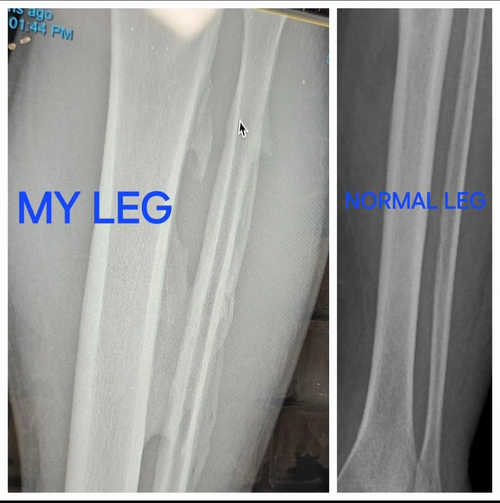

this is sean stricklands tibia and fibula compared to a normal one, you can look this up and find a doctor explaining how theres growth due to repetitive stress on the bone

YES , THats CALLED WOVEN BONE